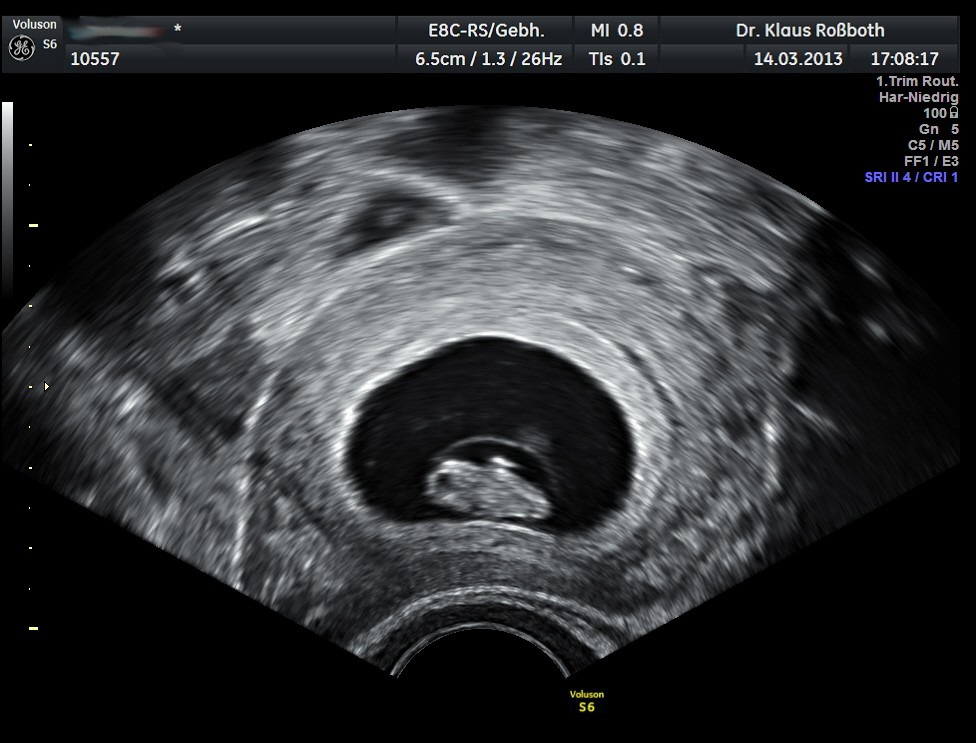

Zweitens: Ultraschall sind keine Kristallkugeln! Die Messungen sind nicht immer hundertprozentig genau. Der Arzt kann den Winkel falsch einschätzen, das Gerät kann nicht perfekt kalibriert sein, oder der Embryo hat sich einfach nur in eine ungünstige Position gerollt, um sich vor dem Blitzlicht zu verstecken. (Babys haben schon in der 8. Woche Humor, das schwöre ich!)

Hier kommt die gute Nachricht! Wenn der Arzt einen Herzschlag sieht, ist das ein gigantisches, leuchtendes, blinkendes Neonschild mit der Aufschrift: "ALLES IST GUT!" Der Herzschlag ist der beste Indikator dafür, dass sich das Baby normal entwickelt. Ein kleiner Embryo mit einem starken Herzschlag ist oft viel beruhigender als ein großer Embryo, bei dem das Herzchen schlappmacht.